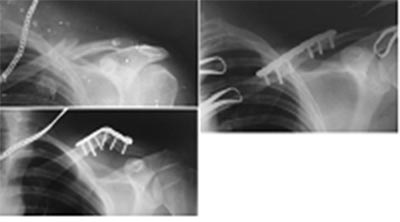

Больной Т.24 года. Косой перелом левой ключицы.Операция (31.12.2014):

Остеосинтез левой ключицы пластиной. 05.05.2015 (через 5 мес.) Во время

поездки на велосипеде получил боковой удар в область плеча, вследствие

падения. Представлены рентгенограммы: до операции, после, после

повторной травмы.Обязательно ли выполнить костную пластику во время

реостеосинтеза.